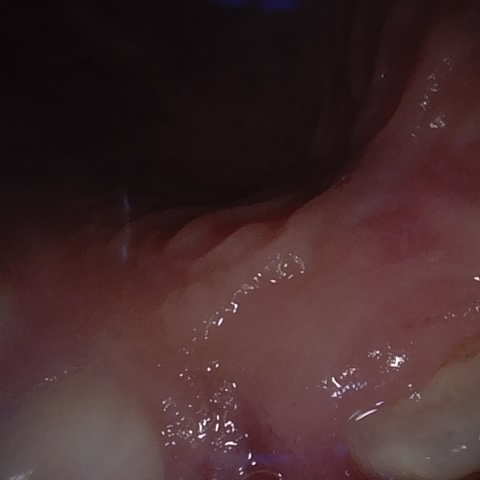

Image 1072 / 1083

NHD39163

Annotated as "Good"

Original Image Rendering Image